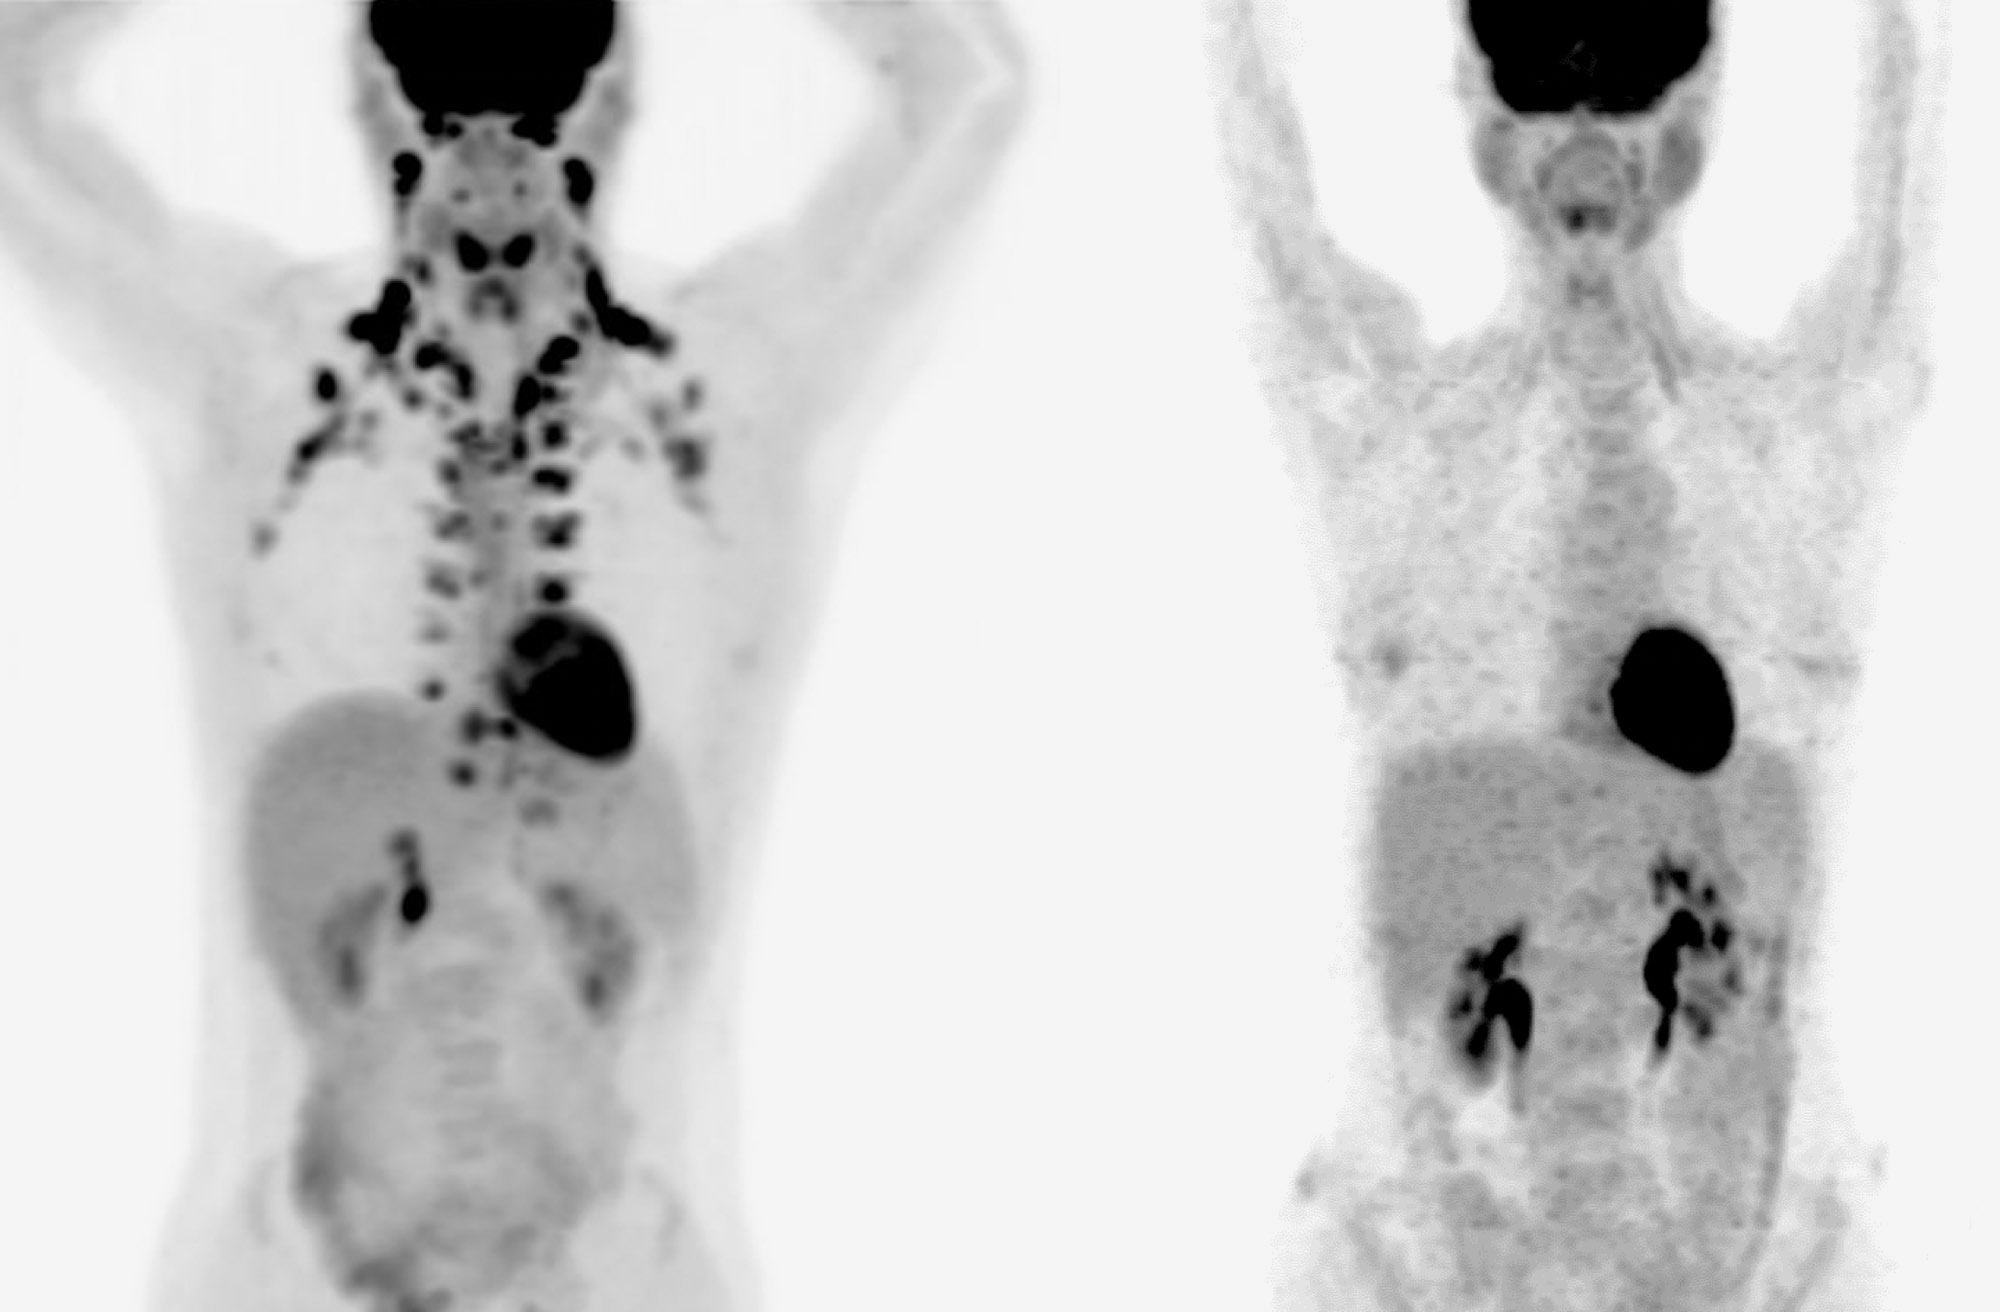

Researchers have been interested in the potential of harnessing brown fat as a treatment for diseases related to obesity. But whether it actually contributes to better health has been unclear. Measuring brown fat requires a type of imaging called a PET scan. Because PET scans use radiation, researchers don’t want to use them in healthy people.

However, people with cancer often undergo PET scanning to track tumors before, during, or after treatment. At some institutions, doctors reading these scans routinely mark areas of brown fat to prevent them from being mistaken for tumors.

A research team led by Dr. Paul Cohen from the Rockefeller University examined such scans from more than 50,000 people seen at Memorial Sloan Kettering Cancer Center during the last ten years. Brown fat was marked on scans taken from about 10% of the patients.